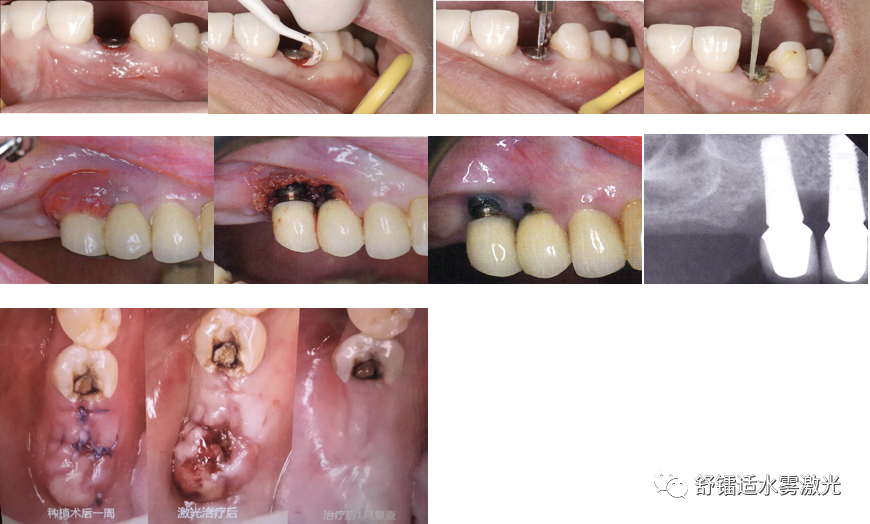

植体周围炎治疗机理:1064nm水雾钕激光能精准去除炎症肉芽组织,还能有效杀灭植体周围炎的多种致病菌。低能量激光还可以加快骨组织修复进程和促进组织愈合,水雾同步输出可以有效保护种植体表面,降低骨组织热损伤。

植体周围炎序列治疗:了解植体牙周情况,采用碳纤维刮治器进行植体表面处理,将没有激活的光纤深入植体牙周袋内,用光纤的尖端沿龈沟轻轻探查,了解龈沟的状况,光纤深入植体牙周袋底后,向上提拉1~2mm,光纤的尖端与植体表面大致平行,并稍向牙龈软组织倾斜,激光进行照射,照射过程中光纤尖端沿水平方向和垂直方向中速移动,滑过所有的上皮组织及炎症组织。如果植体的牙周袋深度小于6mm,每颗牙治疗的时间约30秒;如果植体的牙周袋大于6mm,治疗的时间约45秒;激光照射结束用生理盐水进行袋内冲洗。